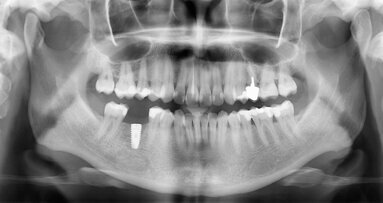

Afin de réaliser une prothèse idéale, l’utilisation d’un guide implantaire est fortement indiquée, en particulier lorsque l’édentement atteint ...